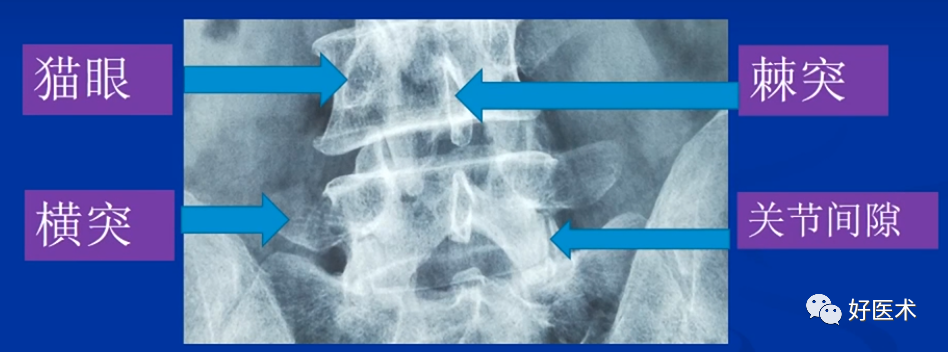

② 腰椎正位片子,猫眼是椎弓根椎狭窄部位的投影,按照操作手册,椎弓根螺钉偏内,容易损伤关节突关节面;

腰椎透视解剖

透视腰椎正位:上下终板成单边;椎弓根(猫眼)对称;棘突居中。

透视腰椎侧位:上下终板成单边;椎弓根上下缘单边;椎体后缘成单边。

实际情况:没有专业的手术透视工作人员;正位和地面垂直;侧位和患者垂直;正位看猫眼内外,侧位看椎弓根上下。